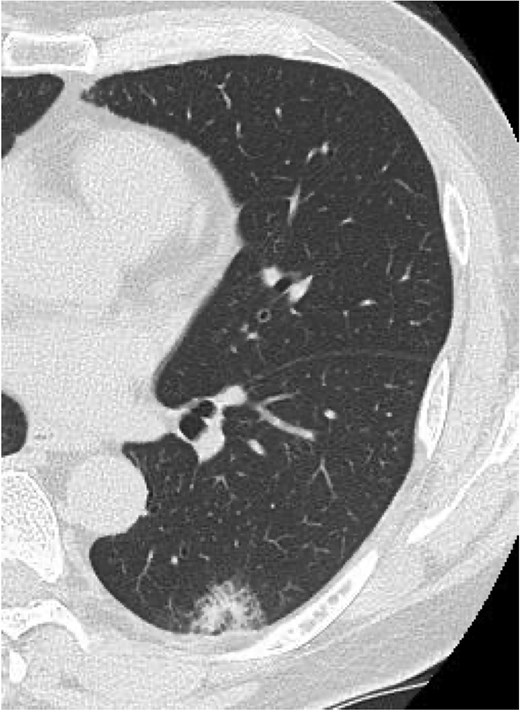

Methylprednisolone pulse therapy (1 g/day for 3 days) was initially administered, followed by oral prednisolone (30 mg). However, oxygen requirements increased to 4 L on POD 31 (Fig. 3). On POD 36, a second methylprednisolone pulse course was initiated with cyclosporine A (150 mg) owing to progressive consolidation on chest imaging (Fig. 2d). Oxygen support was discontinued by POD 38, and he was discharged on POD 52. Follow-up image on POD 104 showed substantial radiological improvement (Fig. 4). Immunosuppressive medications were successfully tapered and discontinued by POD 329. This case was diagnosed as delayed-onset OP as a manifestation of post-acute COVID-19 syndrome, characterized by the biphasic clinical course and distinctive radiological progression occurring weeks after acute COVID-19 infection.

Follow-up chest imaging on postoperative Day 104 showing significant resolution of bilateral consolidations observed during the acute phase of organizing pneumonia.